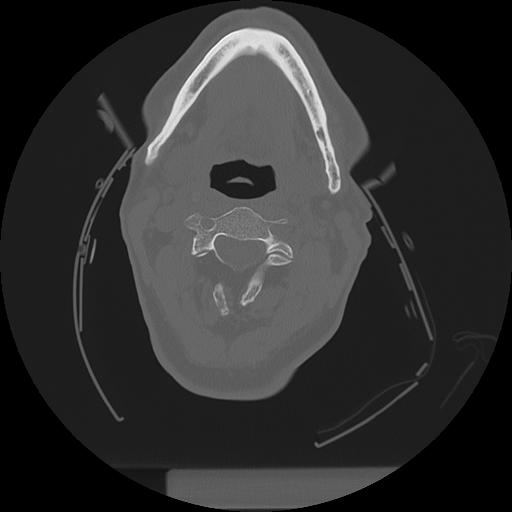

11 HUESO,,Axial,2.0,HUESO,,